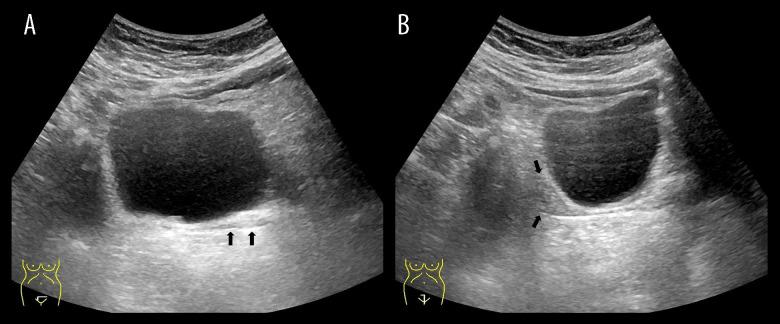

BACKGROUND Mayer-Rokitansky-Kuster-Hauser (MRKH) syndrome is a complex disorder of the female reproductive system that results in an absent uterus and vagina. MRKH syndrome can be an isolated anomaly (typical) or accompanied by other organ anomalies (atypical). Due to the similarity of symptoms with other congenital gynecological diseases, imaging modalities remain the most important tools in establishing the diagnosis by visualizing internal genital and detecting possible organ malformations. CASE REPORT We present a very rare case of a female with primary amenorrhea. Pelvic magnetic resonance imaging (MRI) showed the absence of a uterus and vagina with possible Mullerian remnants, as well as an incidental finding of a right ectopic kidney. Abdominal ultrasonography and chest X-ray showed that the patient also had situs inversus totalis. CONCLUSIONS MRKH syndrome may be associated with situs inversus totalis due to possible early embryologic malformations causing both conditions; however, the exact mechanism is still unknown. This report should serve as a more recent attempt to question whether situs inversus totalis is related to MRKH and to emphasize the importance of imaging modalities, especially MRI, in establishing the diagnosis of MRKH syndrome and the associated malformations.

我们介绍了一例女性原发性闭经的极罕见病例。盆腔磁共振成像(MRI)显示子宫和阴道缺失,可能有苗勒管残余物,以及右侧异位肾的意外发现。腹部超声和胸部 X 线检查显示患者还患有全内脏转位。